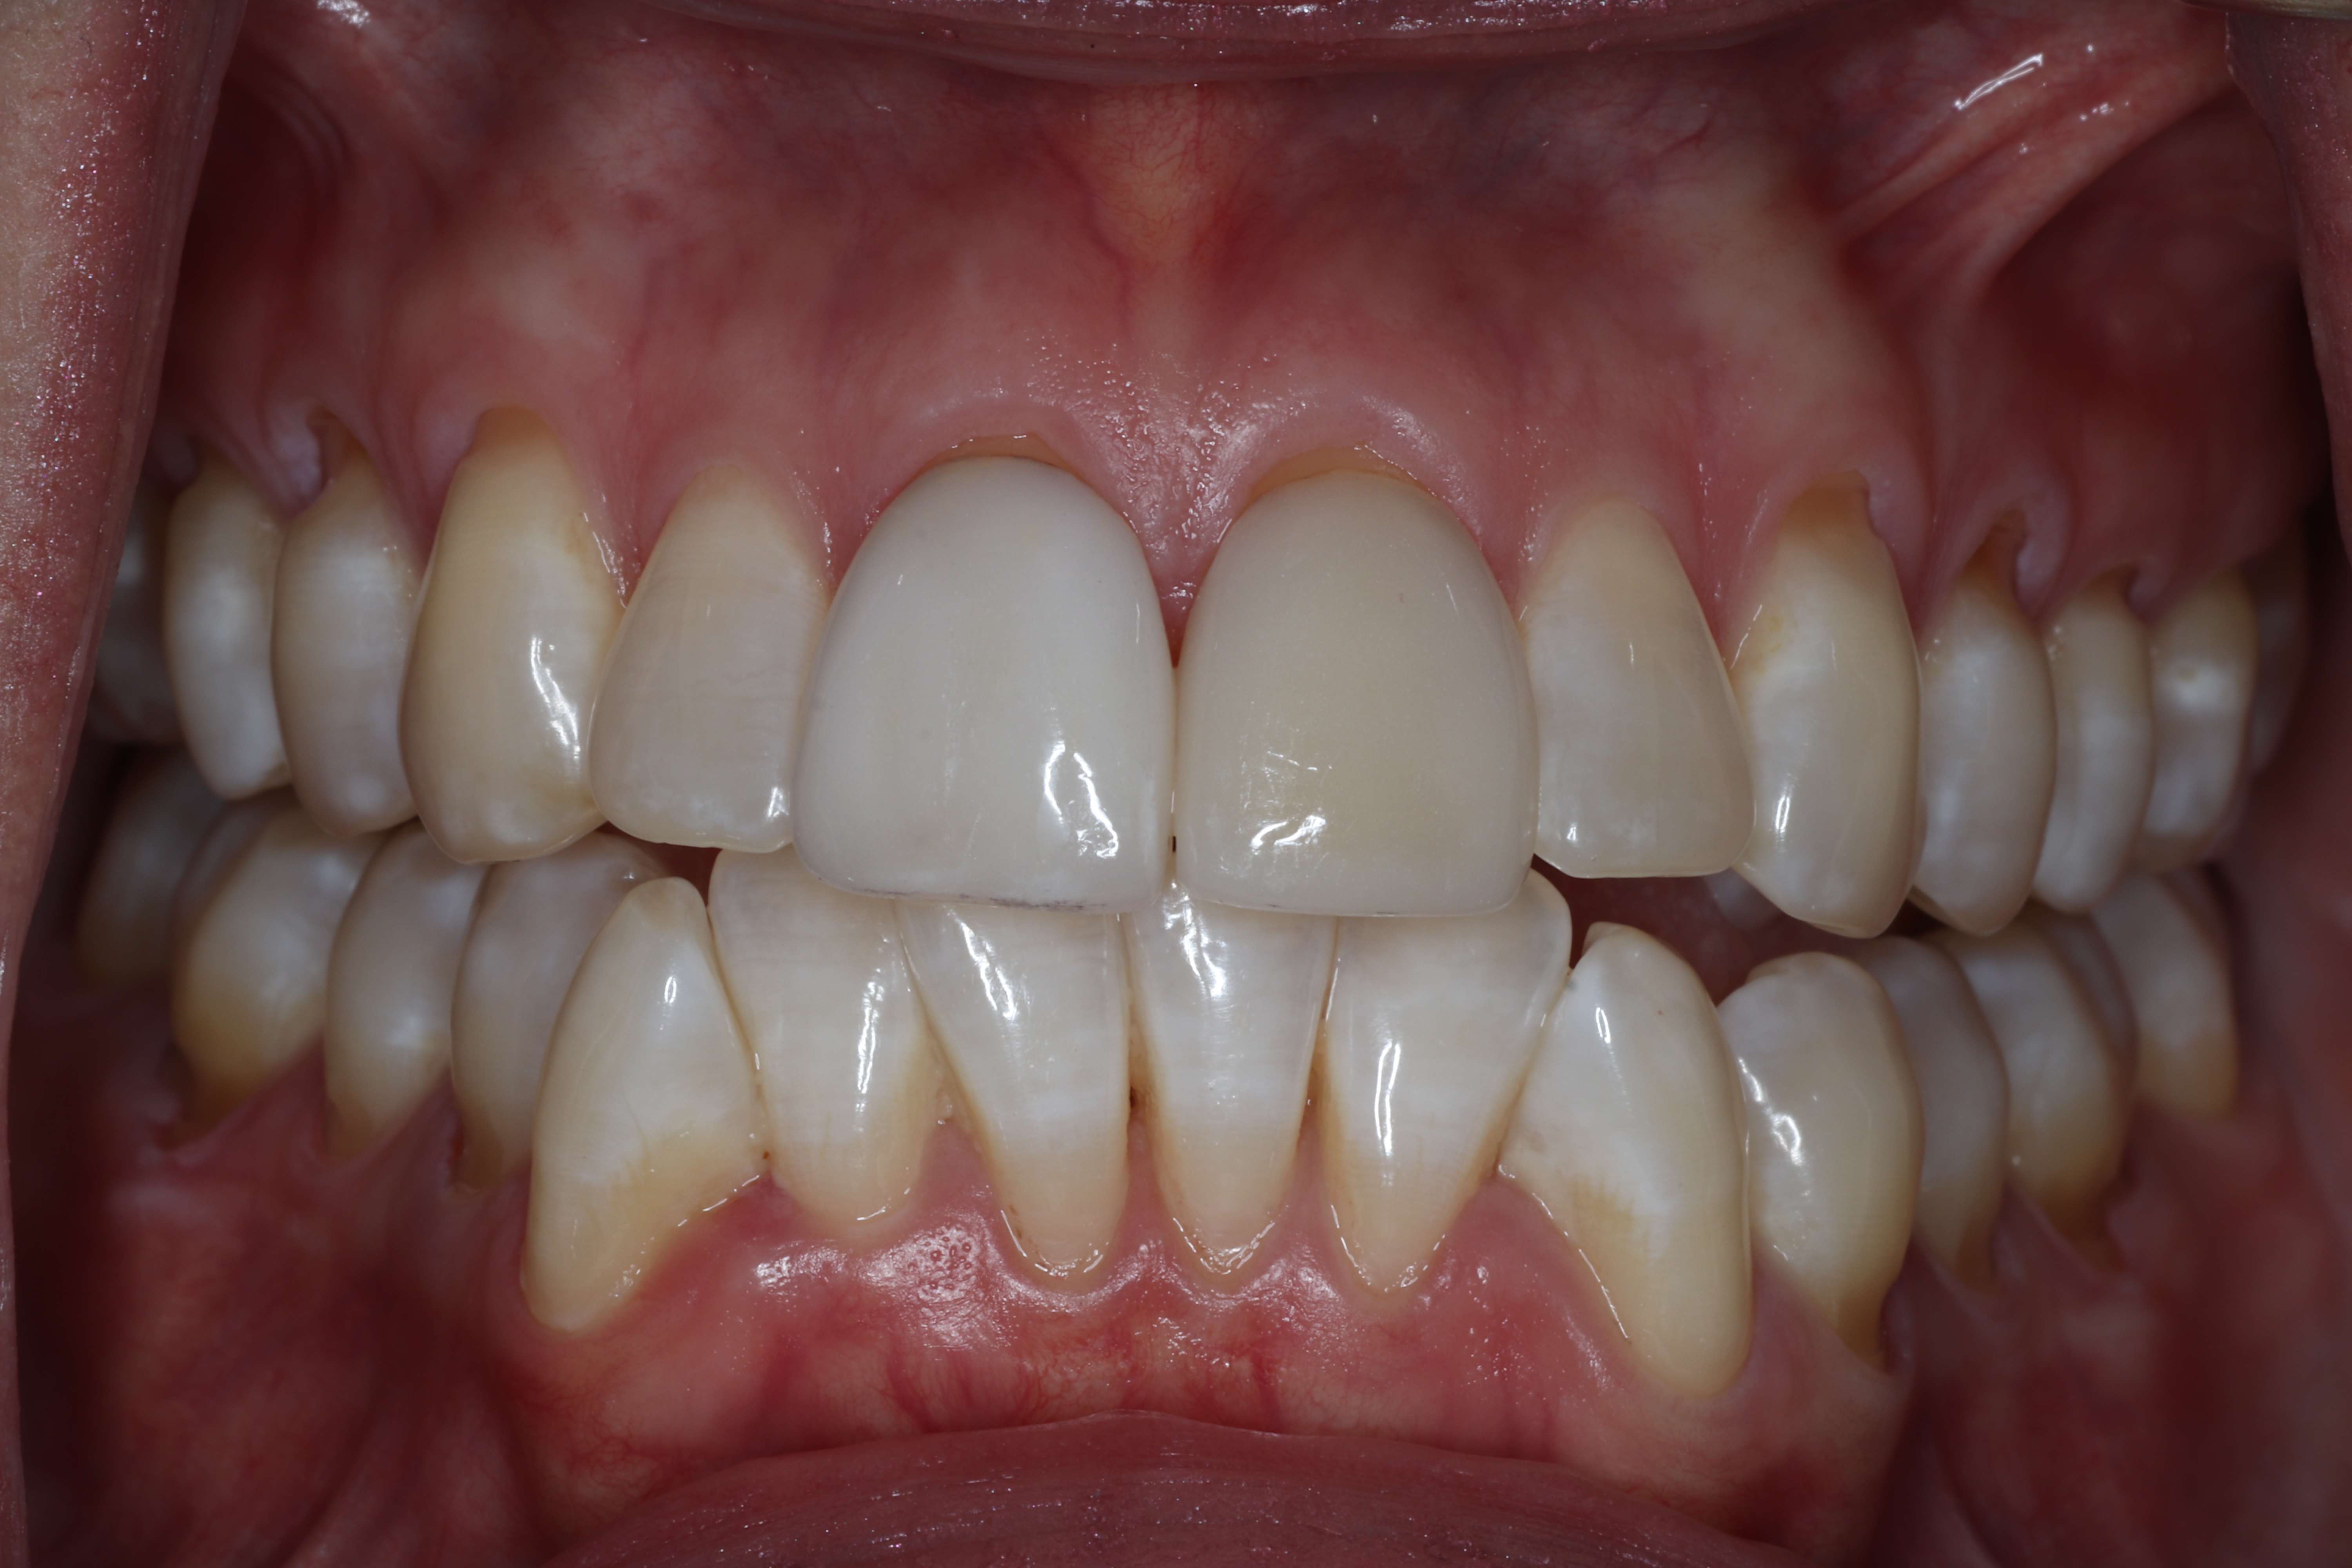

This patient has healthy thick gum tissue. The free gingiva is the cuff surrounding the tooth and the attached gingiva is the thick tissue attached to the bone. Both of these are made of keratinized tissue.

Take a closer look at the difference between the two areas in this patient's mouth. The teeth surrounded by thick, firmly attached protective tissue show no plaque buildup, no inflammation, and stable, healthy gum levels. In contrast, the sites that lack this protective tissue are visibly inflamed and collecting bacteria along the gumline, which is driving progressive recession. Without intervention to rebuild that protective barrier through grafting, the affected teeth would continue to lose gum tissue and bone support over time, ultimately putting them at risk of being lost entirely.